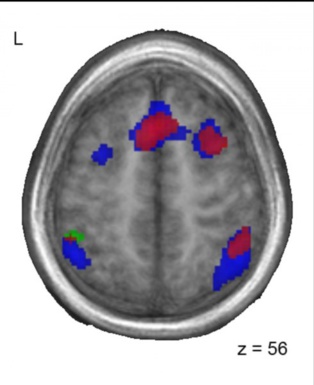

Patrones similares de actividad cerebral entre los bilingües chino-francés (rojo) y los adoptados (azul) cuando realizan una tarea con sonidos de francés. Imagen: Lara Pierce. Fuente: Universidad McGill.

A medida que los niños respondían a las palabras que escuchaban, los investigadores utilizaron imágenes de resonancia magnética funcional (fMRI) para mirar que partes de su cerebro se estaban activando.

Aunque todos los grupos realizaron las tareas igual de bien, las áreas del cerebro que se activaban difirieron entre los grupos. En los niños franceses monolingües sin exposición a China, se activaron las áreas del cerebro que se esperaba que intervinieran en el procesamiento de los sonidos del lenguaje, especialmente el giro frontal inferior izquierdo y la ínsula anterior. Sin embargo, entre los niños que eran bilingües (chino / francés) y los que habían sido expuestos al chino de pequeños y luego habían dejado de hablarlo, se activaron además otras áreas del cerebro, particularmente la circunvolución frontal media derecha, la corteza frontal medial izquierda, y el giro temporal superior bilateral.

Los investigadores observaron que los niños chinos que habían sido adoptados por familias francesas monolingües y ya no hablaban chino, y por tanto eran funcionalmente monolingües en el momento de la prueba, todavía tenían cerebros que procesaban el lenguaje de una manera similar a los niños bilingües.